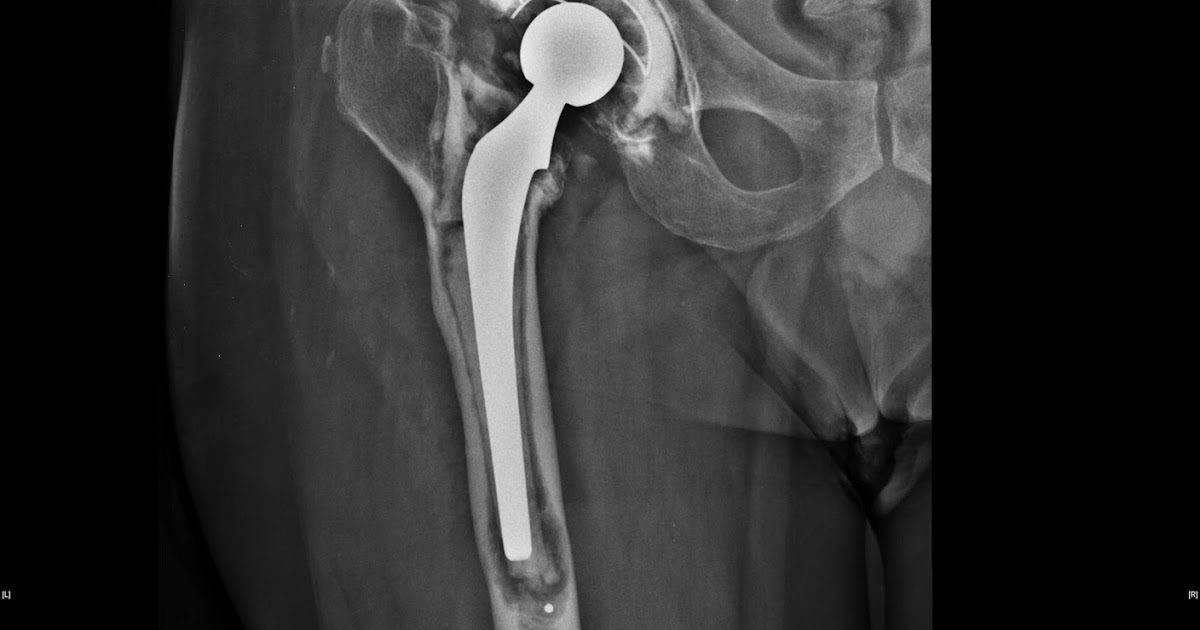

Joint replacement with a prosthetic joint, particularly the hip and knee, has revolutionized the treatment of end-stage osteoarthritis. Instead of patients becoming dependent on wheelchairs and other mobility devices, they can be rapidly restored to full and independent function and mobility. However, osteolysis is a troubling condition that affects a considerable number of patients after joint replacement. Osteolysis basically means bone loss around the prosthetic and unless it is caught early and treated, it can lead to serious problems and may require additional surgery for treatment. Symptoms and conditions associated with osteolysis include the following.

Osteolysis is currently the most common complication followed joint replacement. Most patients appear to recover well from the surgery, and then over the next few years, bone loss around the implant occurs, leading to what is referred to as 'aseptic loosening,' which is loosening of the implant without any infection. Depending on the joint and the type of prosthetic, osteolysis may affect from thirty to sixty percent of patients in the first ten years after joint replacement. It often requires additional surgery to address the issue.

Most patients with osteolysis don't experience any symptoms, and the condition is only observed on follow-up x-rays. However, some patients experience pain with implant movement as osteolysis progresses. In many cases, the pain is experienced as muscle or joint pain distant from the replaced joint. For example, a loosening hip prosthetic can cause thigh and knee pain as the body tries to compensate for the unstable hip joint.